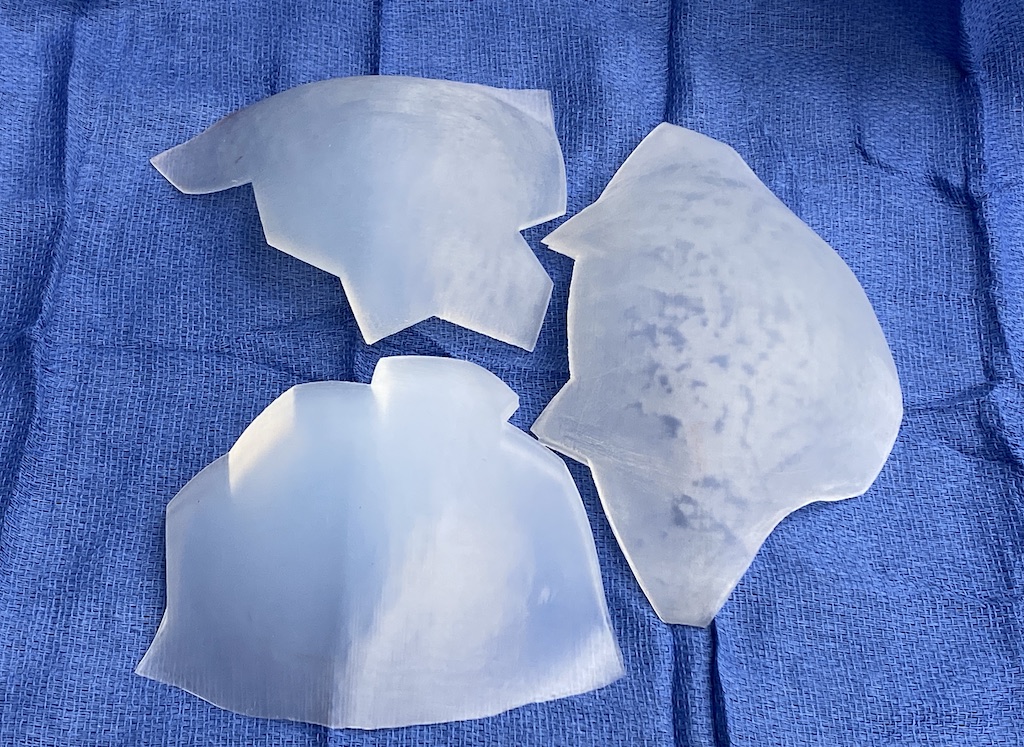

Desire for major head reshaping with a taler and wider head shape.

Placement of large two piece custom skull implant through a sagittal scalp incision.

Desire for major head reshaping with a taler and wider head shape.

Placement of large two piece custom skull implant through a sagittal scalp incision.